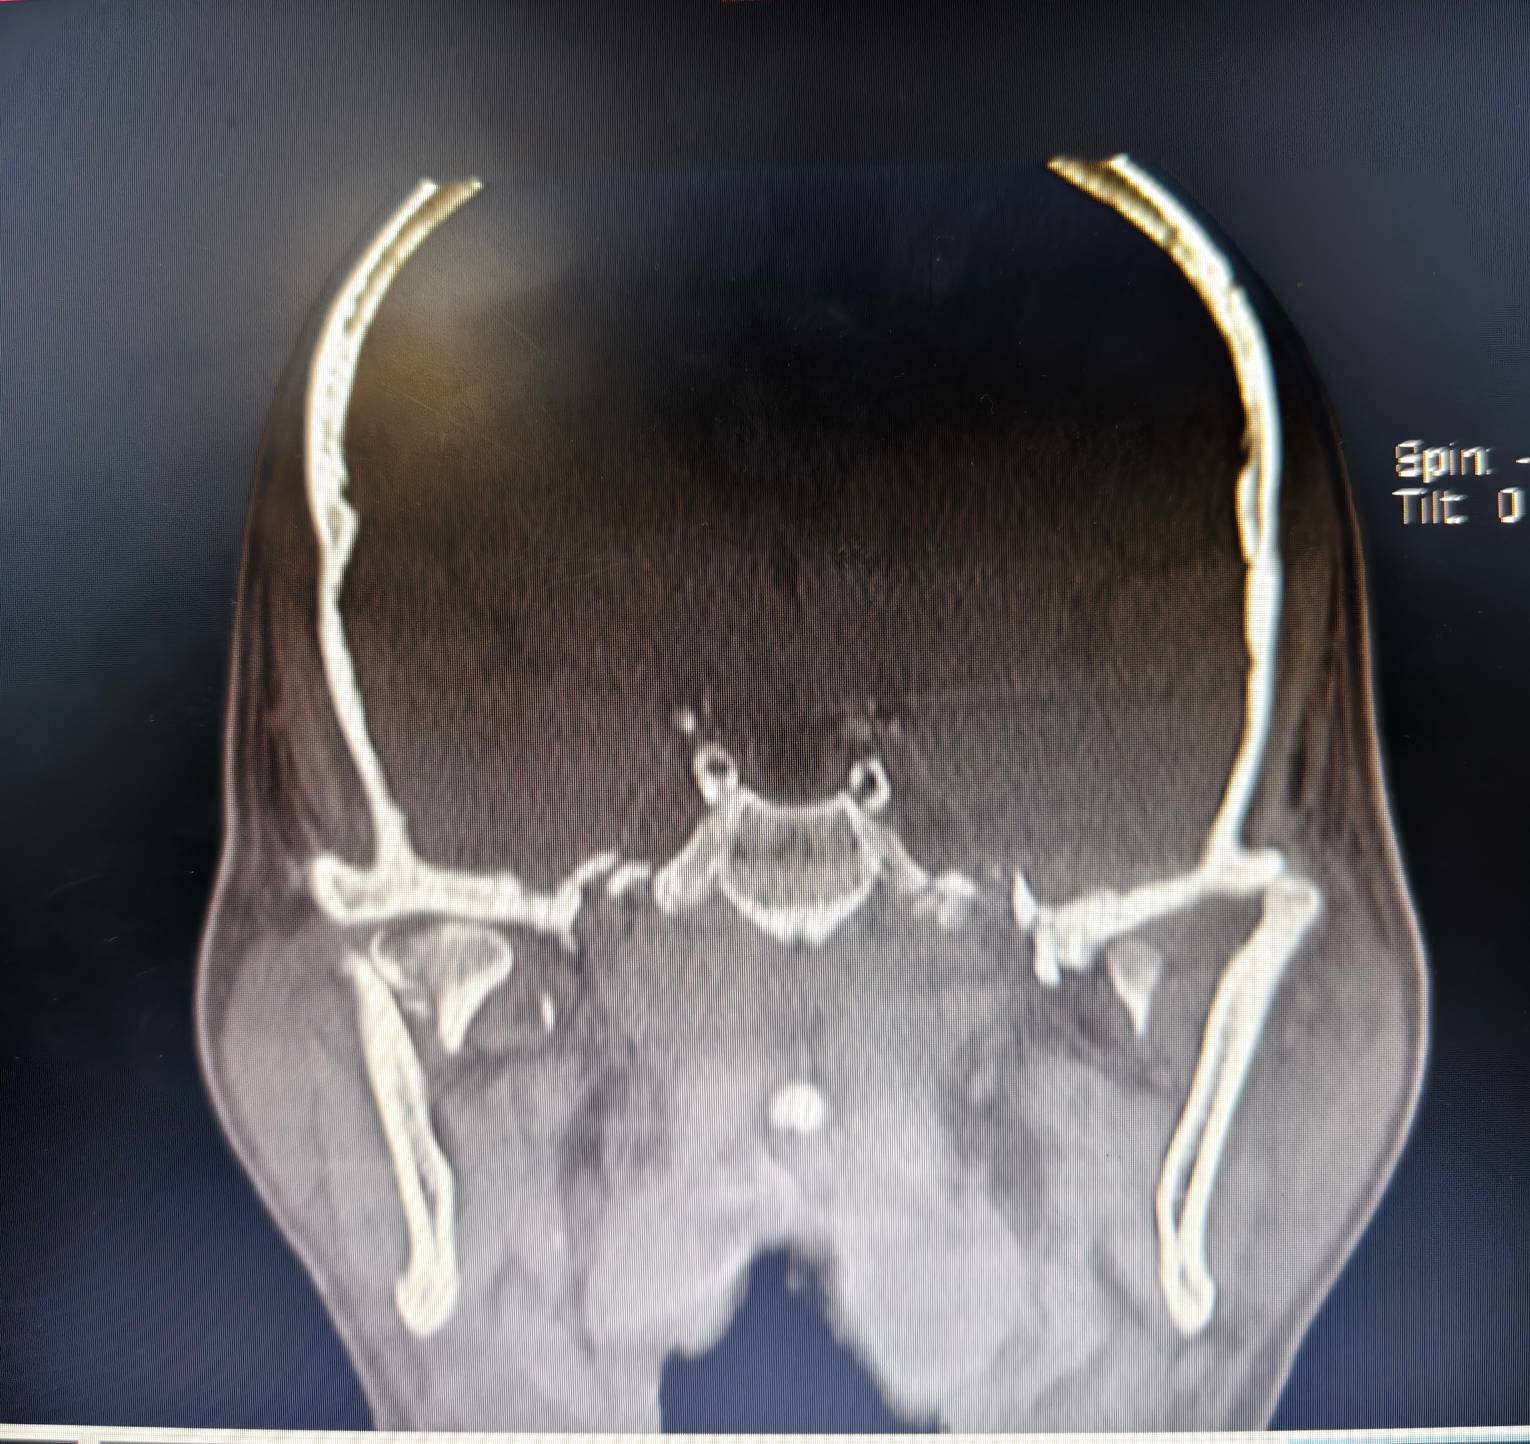

近日,姬先生因高空意外坠落导致全身多处严重骨折,被紧急送至我院救治。经诊断,姬先生头部、颌面、胸部、右髋、右膝等多处骨折,其中颌面为上颌骨多发及下颌骨多发伤,伤情极为复杂,对面容及进食造成极大影响。

姬先生入院后,我院整形外科(颌面骨科)主任胡沛、副主任医师马莉及主治医师田振江诊疗团队高度重视,面对这种高难度手术,科室组织大家进行病情讨论并进行全面评估,精心制定了个体化手术治疗方案。考虑到传统手术方式在面对如此复杂的颌面骨折时难度极大,团队决定借助我院先进的3D打印技术制作,成功打印出了高精度的面颅部创伤模型并进行术前设计及术中辅助复位。

术前